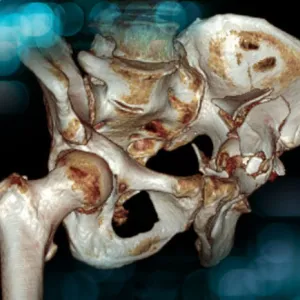

Discover how complex complications were successfully managed using advanced revision techniques, in this challenging case of bilateral hip arthroplasty in a 79-year-old woman.